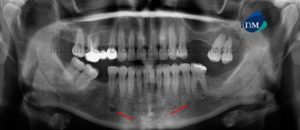

Paciente femenino de 34 años es referido al Instituto de Diagnóstico Maxilofacial para seguimiento de lesión en mandíbula. Se muestra la radiografía panorámica inicial (Figura